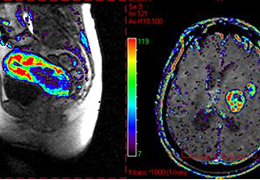

DSC Perfusion

Automated Processing. Quantified Results.

Review all automatically computed DSC maps.

Compare findings through AI-powered ROI statistics.

Export maps and core findings to your PACS instantly.